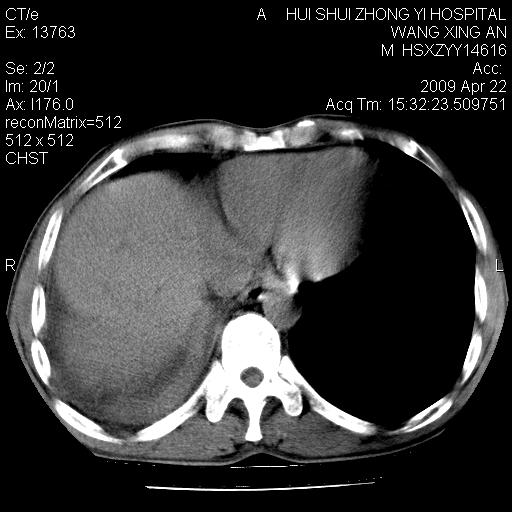

标题: CT19534:患者男、46岁咳嗽、胸痛半月。 [打印本页]

标题: CT19534:患者男、46岁咳嗽、胸痛半月。

1、右下肺中央型肺癌并右肺转移,右肺下叶不张。(肿块围绕右肺下叶支气管生长,致管腔闭塞右肺下叶不张;右肺有结节影)。

2、右侧胸腔积液。

3、右中上肺陈旧性肺结核(右肺见纤维化病灶及点状钙化)。